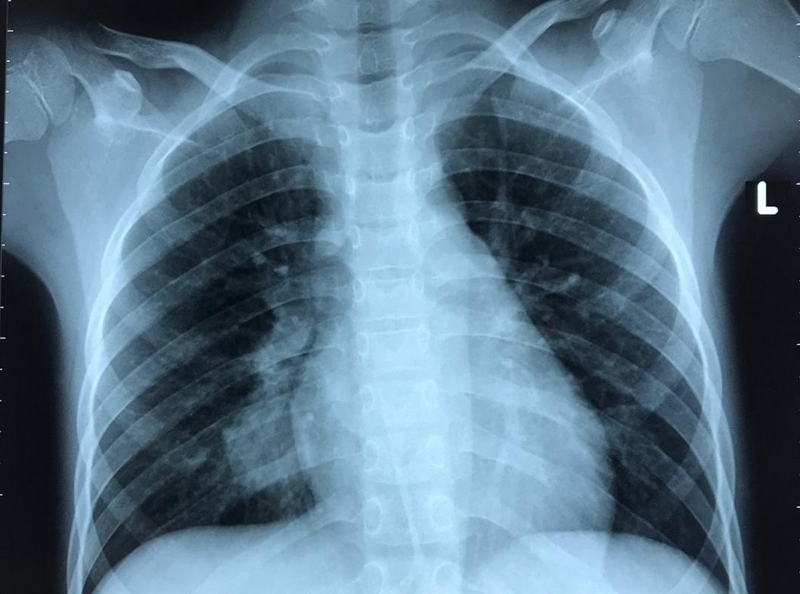

Chụp cắt lớp phổi còn được gọi là chụp CT phổi, là sử dụng công nghệ chụp X - quang để chụp lá phổi từ nhiều góc độ khác nhau, cho ra hình ảnh chi tiết nhất, tránh bỏ sót bất cứ vùng nào. Vì hình ảnh thông qua chụp cắt lớp phổi là hình ảnh 3D nên sẽ giúp bác sĩ theo dõi bệnh tình tốt hơn, hạn chế xảy ra sai sót.

Ung thư phổi là bệnh lý nguy hiểm có thể chẩn đoán thông qua hình thức chụp cắt lớp phổi. Khi này, những khối u do ung thư dễ dàng nhìn thấy cũng như xác định vị trí tương đối chính xác, hỗ trợ cho quá trình điều trị hoặc phẩu thuật sau đó.